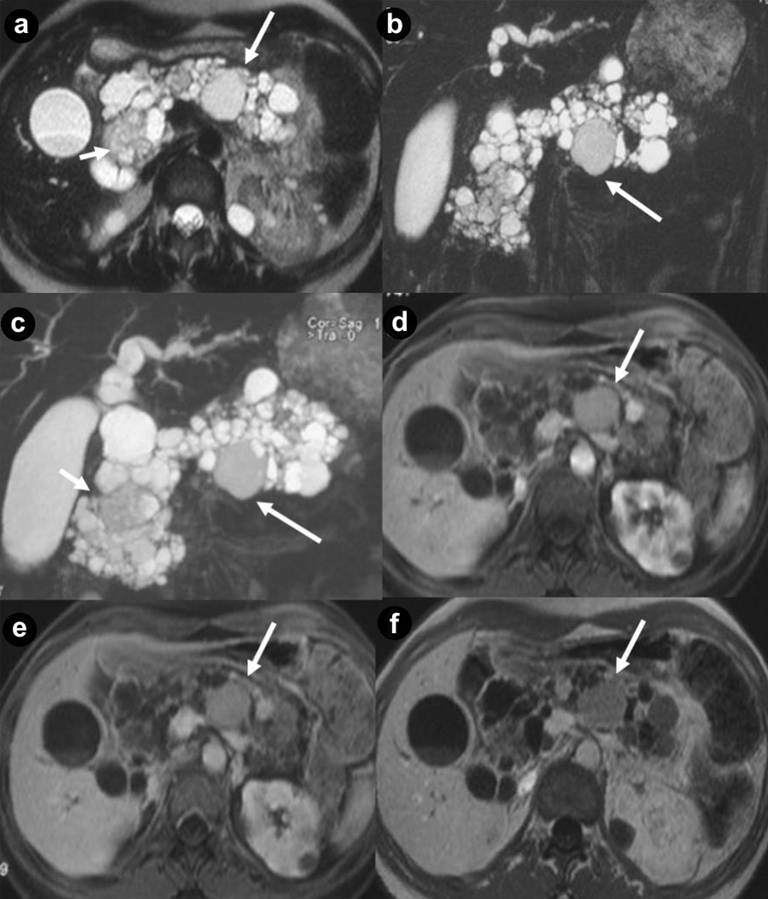

Figure 1. Pancreatic unilocular cysts (a. b. c. Case#1: 35-year-old man with VHL disease). Pancreatic microcystic serous cystadenoma (d. e. f. Case#2: 30-year-old man with VHL disease). Axial (a. d.) and coronal (b. e.) T2-weighted MR images; coronal (c.) and axial (f.) 3D volumetric gradient-echo T1-weighted fat suppressed images after intravenous contrast medium administration during arterial pancreatic phase of contrastographic dynamic study. Case#1. Multiple fluid, cystic lesions of pancreatic parenchyma with different size and site (arrows), hyperintense on T2-weighted MR images, are present (a. b. c.). Cystic lesions do not communicate with the main pancreatic duct, which appears not dilated. The cystic walls do not show enhancement after intravenous contrast medium administration (c.). In the upper pole of the left kidney (a.) a complex cystic mass (black arrow) is detected. Case#2. A lobulated fluid mass, with thin walls, hyperintense at T2-weighted images (d. e.), is present in the body of pancreatic gland (arrowheads). Inside the mass, containing multiple fluid cystic areas, multiple radially aligned thin septa are visible (spongy appearance or honeycomb pattern). The septa and the peripheral walls enhance after intravenous gadolinium administration (f.). The septa are well depicted on coronal T2-weighted MR image (e.) but the central scar is not visible. In the remaining portion of pancreatic gland multiple cystic, fluid, round lesions, with different size and site and without enhancement after intravenous contrast medium administration (f.), are present. |

Thirty-four pancreatic lesions were found in the 23 patients. In qualitative analysis, the MR imaging findings were: 6 (26.1%) unilocular fluid cystic lesions (Figure 1abc): 3 (13.0%) in pancreatic head, 3 (13.0%) in pancreatic body-tail; 11 (47.8%) serous micro- or micro/macro-cystic cystadenomas (Figures 1def, 4, and 5): 1 (4.3%) in pancreatic head, 2 (8.7%) in pancreatic body-tail (Figure 1), 8 (34.8%) diffuse (Figures 4 and 5); 8 (34.8%) neuroendocrine solid tumors: all of them non-functioning NET and hypervascular during arterial pancreatic phase of contrastographic dynamic study (Figures 2, 3, 4, and 5), 4 (17.4%) at pancreatic head (Figures 2ab; 3ace, and 4), 4 (17.4%) at pancreatic body-tail (Figures 2cd and 5); 1 (4.3%) cystic non-functioning NET, diffuse in all pancreatic gland (Figure 6); in 4 (17.4%) cases association of non-functioning NET and pancreatic cystic lesions (3 cases of association of non-functioning NET and serous cystadenoma (13.0%); 1 case of association of non-functioning NET and pancreatic simple cystic lesion (4.3%)) were present (Figures 4 and 5). Vascular invasion was not detected in any patients.

The average of maximum diameter of these cystic lesions was 44 mm (Figure 1abc).

At MR imaging [3, 9, 15, 16, 21] pancreatic cysts appear hypointense on T1-weighted images and hyperintense on T2-weighted images lesions (Figure 1ab), with no enhancement after intravenous gadolinium contrast medium administration (Figure 1c).

In microcystic serous cystadenomas, MR images [3, 15, 16, 17] show a circumscribed, encapsulated mass, with plurilobulated margins and thin walls, hyperintense on T2-weighted (Figures 1de, 4abcd, and 5abc) and hypointense on T1-weighted images, with multiple and radially aligned thin septa, hypointense at T2-weighted images. A central fibrous scar with calcification is frequently present. Peripheral wall and septa enhance after intravenous gadolinium administration (Figure 1f, 5def). The septa are well depicted on T2-weighted MR images but the central scar is not. The use of a gradient-echo pulse sequence with a long echo time may bring out the susceptibility effects from the calcified scar. So, the fluid mass results composed of a grapelike cluster or “honeycomb pattern’’ of uniformly sized cysts with a diameter of 2 cm or smaller.

In our series pancreatic serous cystadenomas were present at MR imaging in 47.8% of patients with VHL disease (Figures 1def, 3bdf, 4, and 5).

To obtain pathological specimen and histological confirmation of MR imaging findings we retrospectively evaluated symptomatic patients only (13 out of 23; all of them submitted to surgical procedure) and we do not know the pathological specimen of the remaining patients not submitted to surgical procedure(10 out of 23). It can explain the high frequency of serous cystadenoma in our series of VHL patients, differently from other study cases. The average maximum diameter of these lesions was 56.6 mm and 34.8% of these cases were diffuse in all pancreatic gland (Figures 4 and 5); 8.7% were localized at pancreatic body-tail (Figure 1def) and 4.3% were localized at pancreatic head (Figure 3bdf). According to Agarwal et al. [22], in 13.0% of our cases, the serous cystadenoma (all of them diffuse in all pancreatic gland) were associated to hypervascular solid neuroendocrine tumors (Figures 4 and 5).